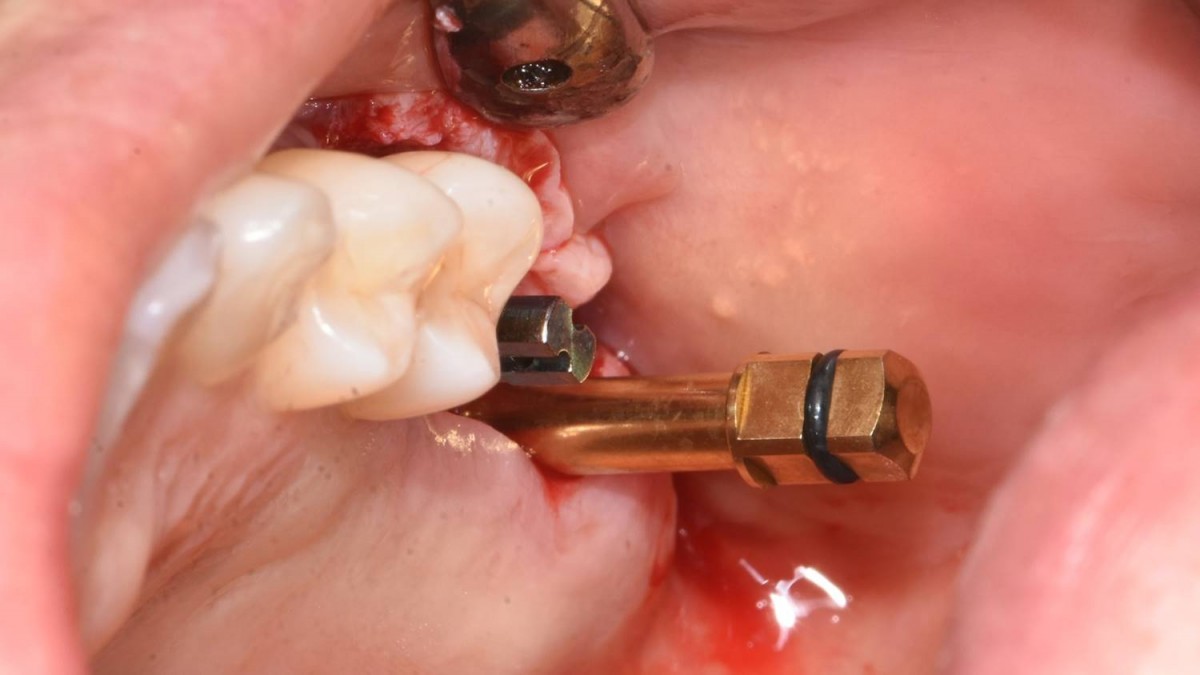

A 55-year-old female patient had

bilateral problems in both jaws.

It was decided to proceed with implant-supported restoration in the left molar part first.

She had been taking hypertension medication for a long time.